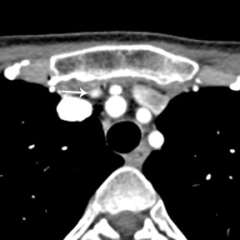

How do imaging results (scans) influence eligibility for re-do parathyroid surgery? The importance of parathyroid 4-D CT.

To a significant degree, re-do parathyroid surgery is driven by the presence of a clear anatomic target. Since 2012, UCLA Endocrine Surgery has employed parathyroid 4-D CT in the planning of all reoperations for primary hyperparathyroidism. [see video on parathyroid 4-D CT]. 4D-CT provides the highest possible anatomic detail and affords the highest likelihood of achieving a safe and successful second operation.

For us, 4D-CT technology has been a "game changer," enabling >95% of patients with failed initial operations to become eligible for reoperation, greatly aiding our ability to counsel patients on surgical strategy, and allowing us to complete reoperations in a much shorter time. Many patients are understandably disappointed and wary after their first parathyroid operation has failed. 4D-CT allows us to sit down with the patient and walk through a series of high-resolution images so that the patient and their family can get a clear understanding of the surgical plan.